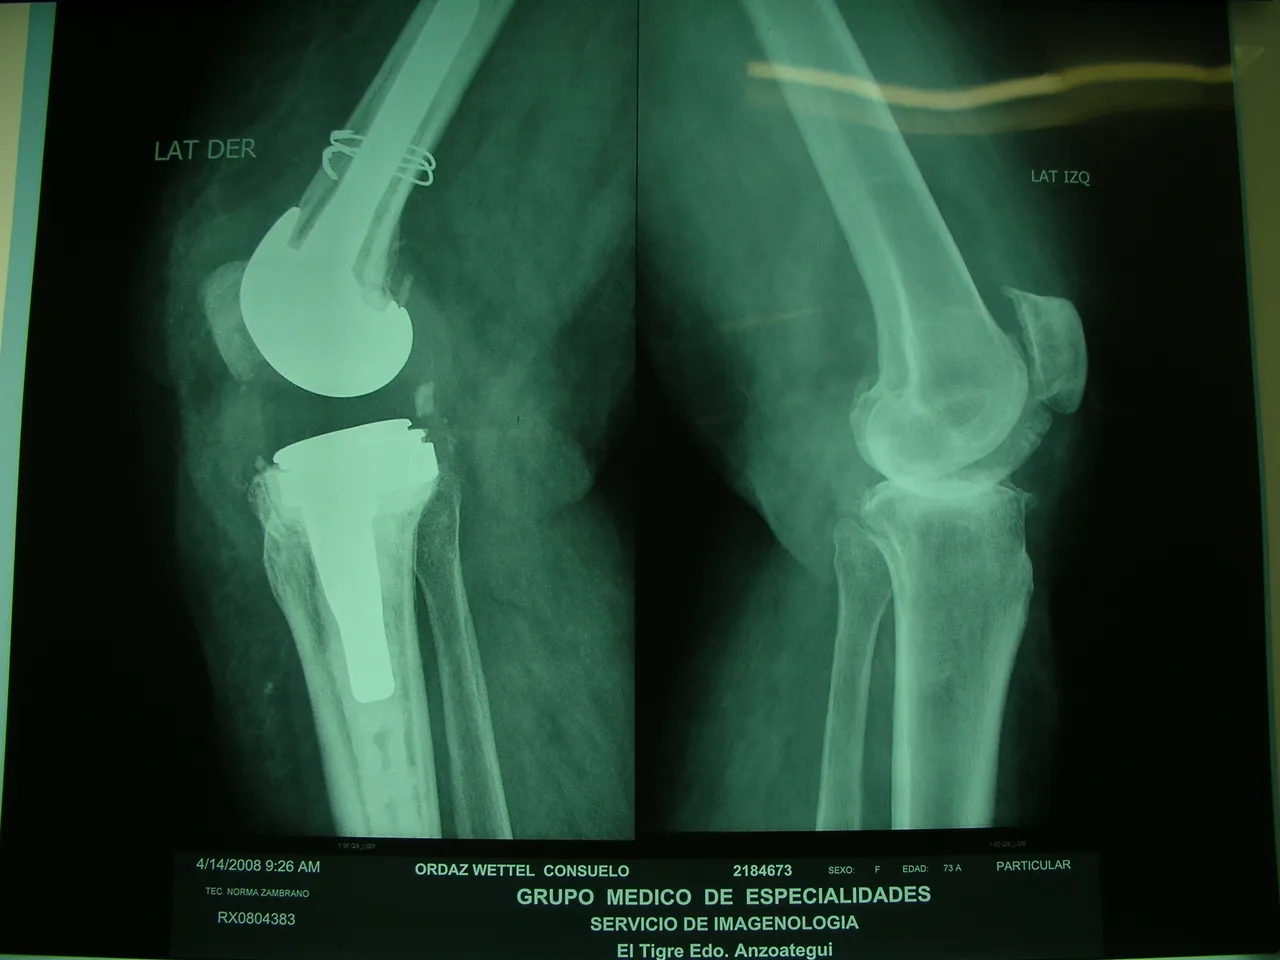

Total Knee Replacement (TKR) The most common knee surgery is total knee replacement, a procedure in which the damaged knee joint is removed and replaced with metal, ceramic and/or plastic components. The knee is the most commonly operated joint, we have already had some previous post talking about this.